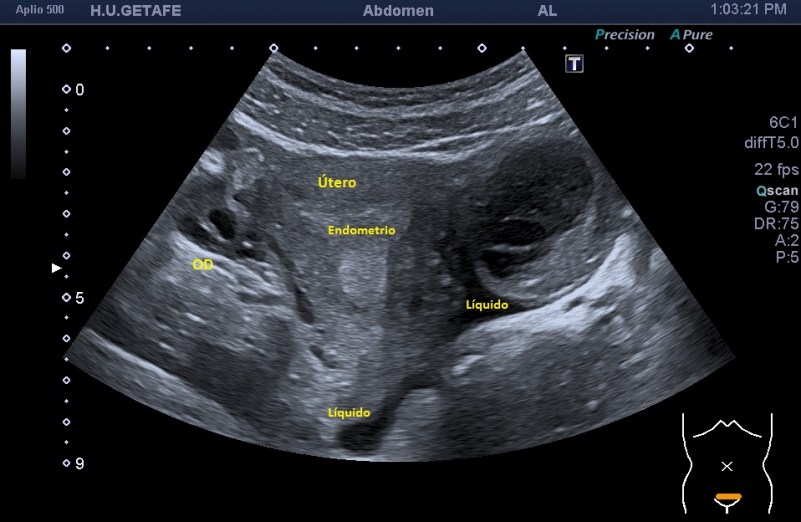

En este corte transverso llama la atención una imagen redondeada hacia el lado izquierdo del útero, de gran tamaño respecto del lado derecho. Es heterogénea y tiene densidad quística y contenido ecogénico, no se sabe su etiología.

En la imagen 4 y 5 te detallo anatomía con y sin referencias para que te ubiques bien y veas todo con detalle, mira:

La anatomía imagen ecográfica que acabas de observar revela un ovario derecho con sus fóliculos anecoicos, normales. En cambio, el ovario izquierdo, o en su teórica ubicación existe una estructura como la que te he comentado anteriormente, de aspecto quístico con contenido y además como muy bien puedes observar, con septos en el interior de la lesión.

Fuera de la lesión, a su alrededor, observamos líquido, a valorar por el radiólogo.

El endometrio se ve aumentado de tamaño tanto en transverso como en longitudinal, parece en fase secretora.